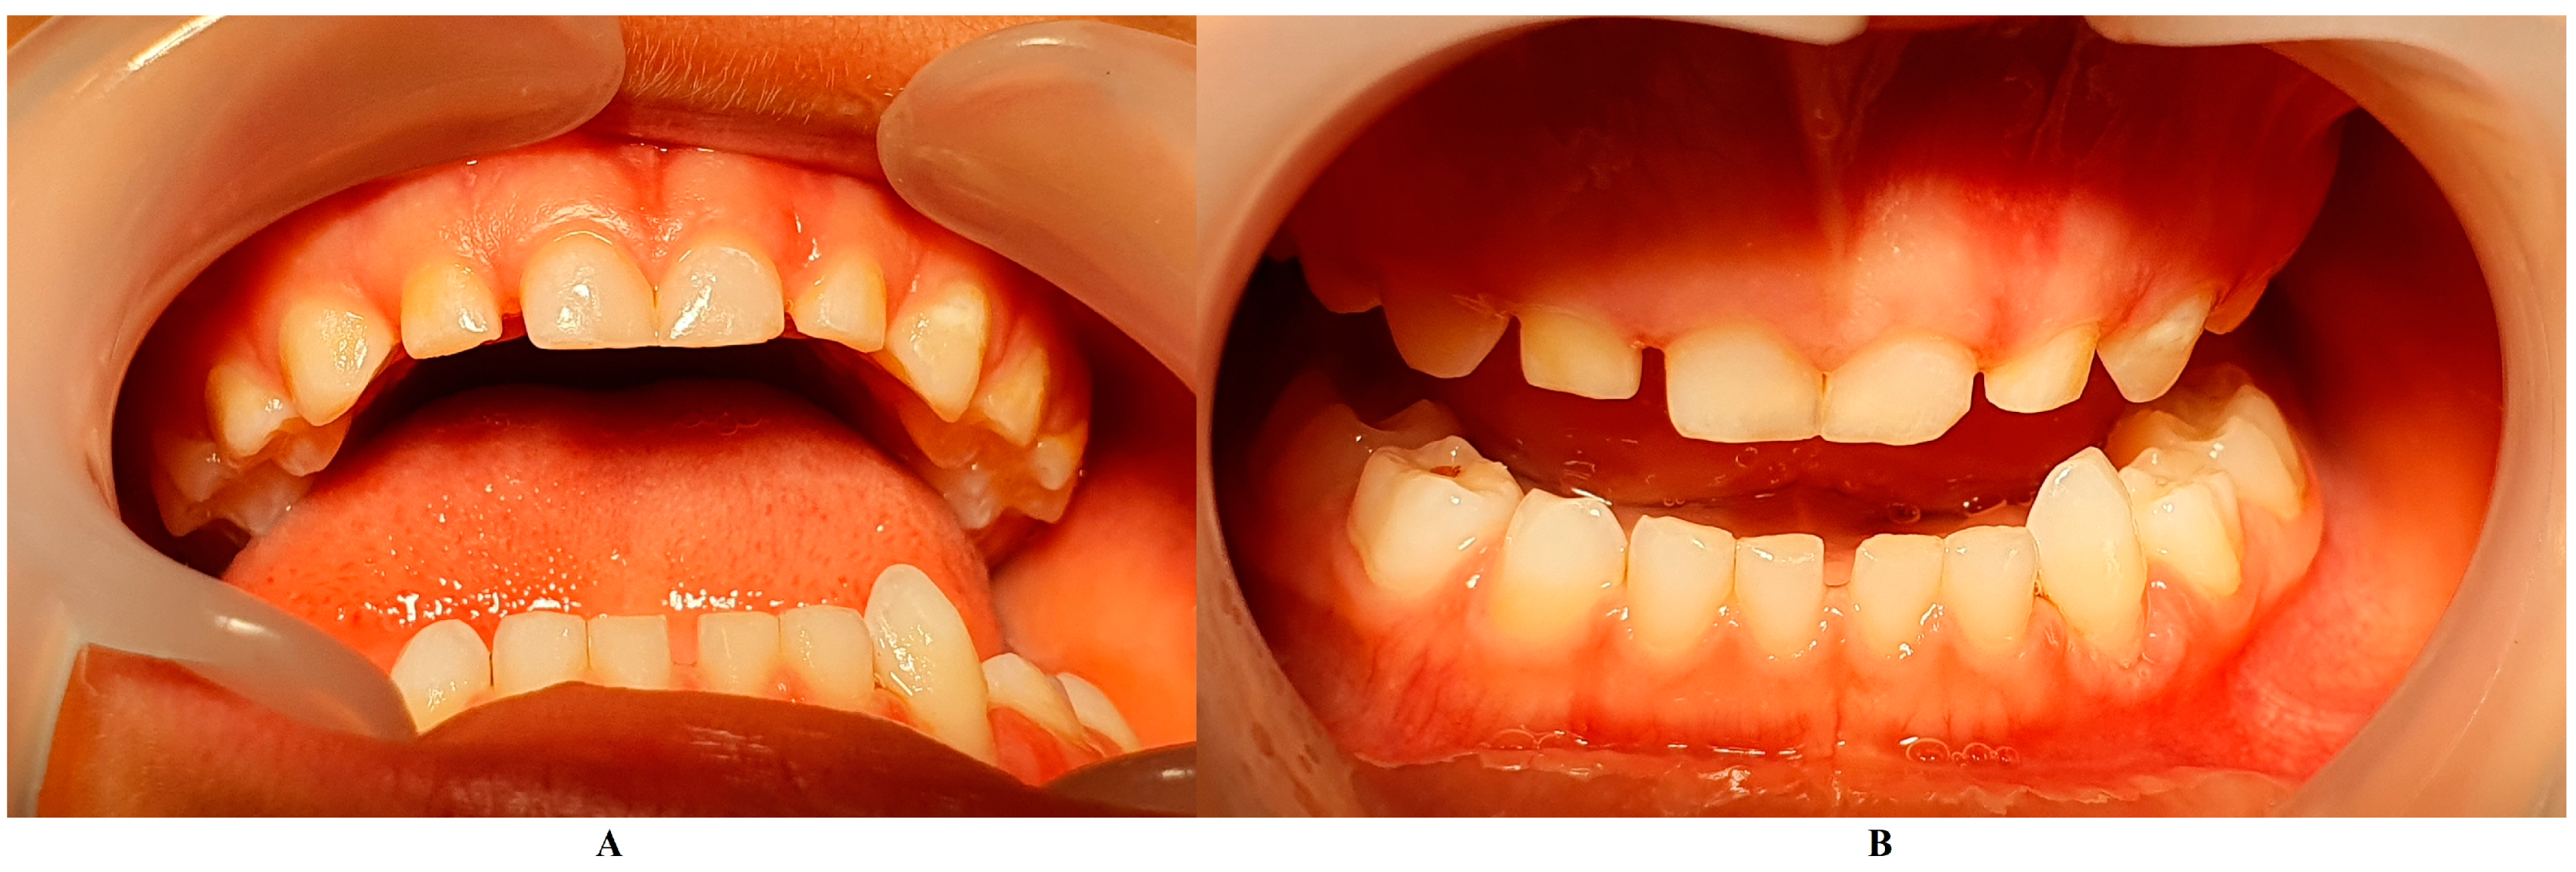

The family spent the summer holidays in Klausenburg/Cluj-Napoca (Romania), where they consulted another dentist (2 August), since tooth movements increased, and they were concerned about the outcome. After the clinical examination and review of previously available radiographs, blood tests, and the patient’s clinical history, a diagnosis of Stage IV grade C localized periodontitis/LPP was established (hypophosphatasia/hyperphosphatasia was excluded from the beginning, despite the fact that genetic test results were not yet available) (Figure 2 and Figure 3). These two figures show the case in early August, with a localized hyper-eruption of the tooth due to extended periodontal loss, inflammation in periodontal pocket, and hyper-immune response. We must emphasize that till early August, no visible signs of orthodontic problems (e.g., hyper-eruption) were found after multiple clinical examinations. The earlier X-ray examination (from early June, Figure 1) was taken into consideration when the diagnosis of Stage IV grade C localized periodontitis/LPP was formulated. To confirm the laboratory diagnosis and identify the type of bacteria involved, a periodontal pocket bacterial test sample was taken (laboratory confirmation, 3 August), and in the meantime, professional oral hygiene and an adjuvant topical combination of amoxicillin and metronidazole was applied for a period of 10 days (due to advanced surrounding bone loss). The periodontal bacteria pocket test came positive, with increased levels of Fusobacterium nucleatum/periodonticum and Capnocytophaga spp. (16 August) confirming the Stage IV grade C localized periodontitis/LPP diagnosis. Because the tooth movement was significant by the time of LPP diagnosis due to advanced periodontal support loss, the tooth was lost at the beginning of September (Figure 4).

Figure 2.

(A,B) Intra-oral cavity general aspect (in early August) with the localized temporary canine problem that led to the LPP diagnosis.

On the other hand, when the first Stage IV grade C localized periodontitis/LPP diagnosis was established (2 August), the clinical examination showed an increased mobility of the temporary lower left canine due to massive bone and periodontal ligament loss, associated with a localized inflammation of the free gingival margin around the tooth, and with small amounts of dental plaque due to difficulties with oral hygiene (Figure 2 and Figure 3). No other plaque deposits, inflamed gingiva, or teeth mobility issues were detected during the clinical examination. When this information was correlated with the radiological examination from two months prior (19 June, Figure 1), with localized bone loss, the diagnosis based on clinical and radiological data was confirmed, with no need for further radiological examination. Moreover, the blood test with higher levels of lymphocytes [2,14] also confirmed Stage IV grade C localized periodontitis/LPP diagnosis. To assess the periodontal pocket bacteria responsible for this atypical LPP case (i.e., temporary molars/incisors are usually involved [1,2,10], rather than the canine, as in this case), a canine periodontal sulcus secretion test was sampled and sent to the laboratory.

A rapid Stage IV grade C localized periodontitis/LPP diagnosis is essential, since the aggressive auto-immune response to bacteria can rapidly lead to a resorptive process [1,2,3,4,5,6,7,8,9,11]. Thus, a simple bacterial test to identify the pathogenic bacterium types would provide both diagnostic confirmation and justification for antibiotic treatment [2,3,11,12,13,14,15]. If LPP disorder is identified early, there is time to wait (i.e., usually up to two weeks) for lab test results, and only then should antibiotic therapy proceed [5,6,9,10,16,17,18]. However, if the LPP diagnosis is late (as it was herein), antibiotic treatment must be started, with a combination of two large-spectrum antibiotics (amoxicillin and metronidazole) to cover most bacterial types [5,6,9,10,16,17,18]. It must be emphasized that LPP usually comes without or with very few plaque deposits (as the case herein showed—see Figure 1, Figure 2, Figure 3 and Figure 4), with little influence over surrounding gingival inflammation [1,2,4,5,6,7,8,9,10].